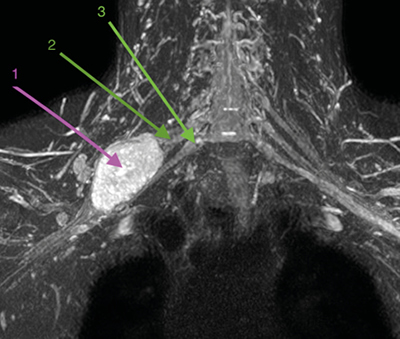

Los schwannomas de plexo braquial son tumoraciones desarrolladas a partir de las vainas neurales de rara presentación, pero evolución benigna. Pueden ocasionar clínica, generalmente de tipo neuropático, por crecimiento local con el consiguiente efecto compresivo de estructuras neurales nobles como las raíces del plexo braquial.

Presentamos el caso de un paciente diagnosticado de schwannoma de plexo braquial con efecto compresivo creciente, a quien se le plantea tratamiento con toxina botulínica en los músculos escalenos.

Brachial plexus schwannomas are tumors developed from the neural sheaths of rare presentation, but benign evolution. They can cause symptoms, generally of the neuropathic type, due to local growth with the consequent compressive effect of noble neural structures such as the roots of the brachial plexus.

We present the case of a patient diagnosed with brachial plexus schwannoma with increasing compressive effect who was treated with botulinum toxin in the scalene muscles.